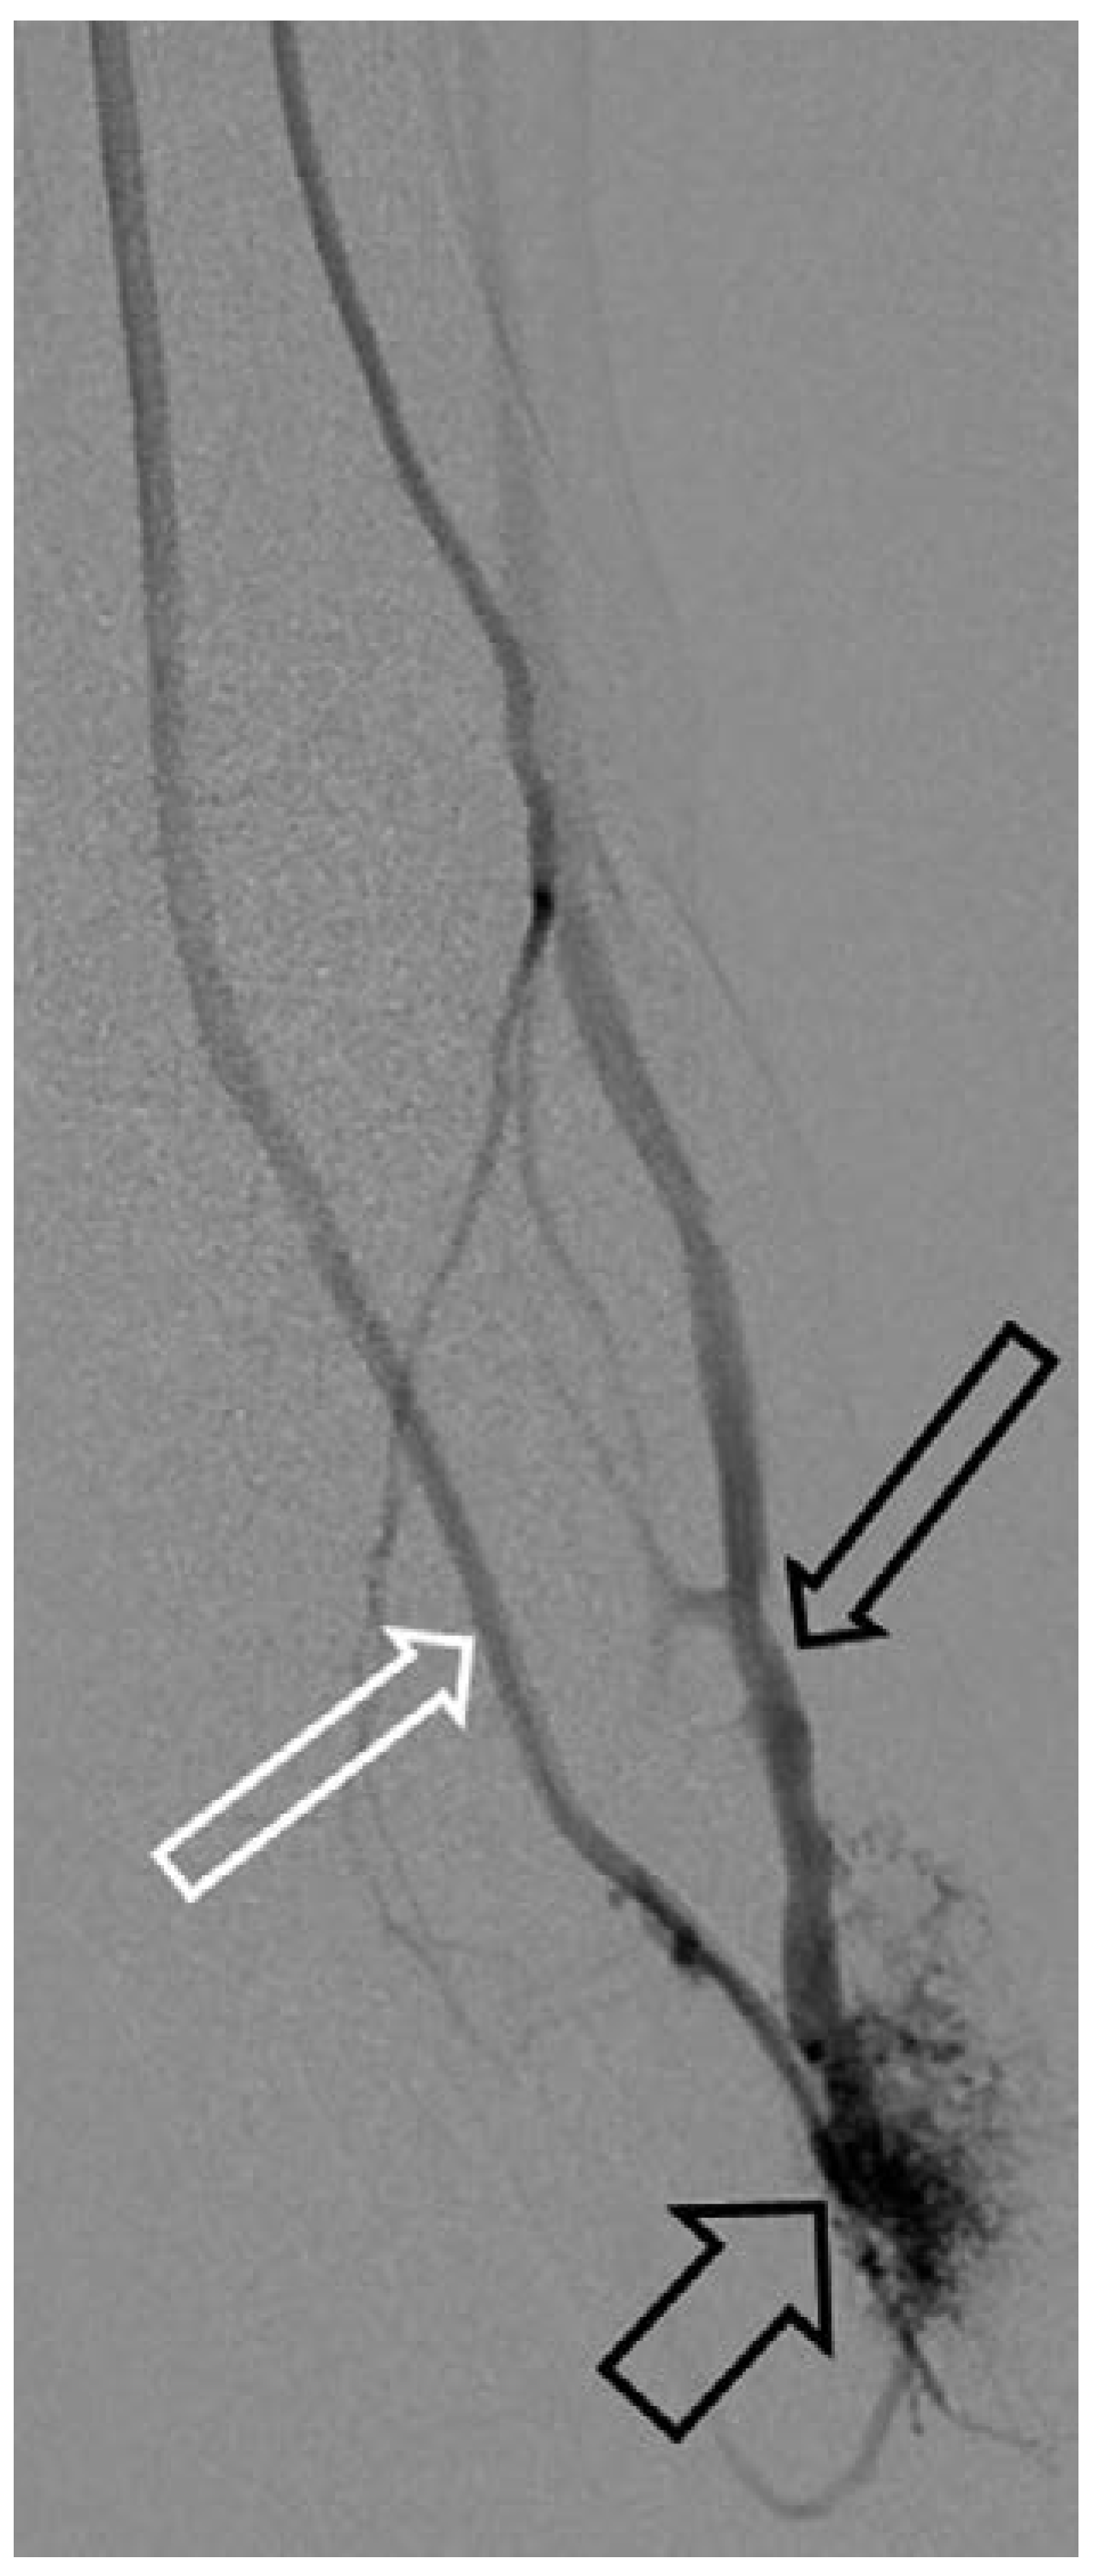

Arteriovenöse Malformation